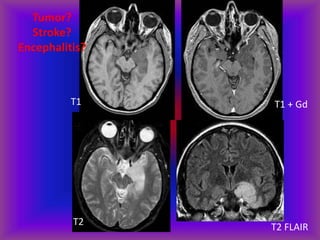

T1 + Gd T2

T1 T1 + Gd

T2 T2 FLAIR

Tumor?

Stroke?

Encephalitis?